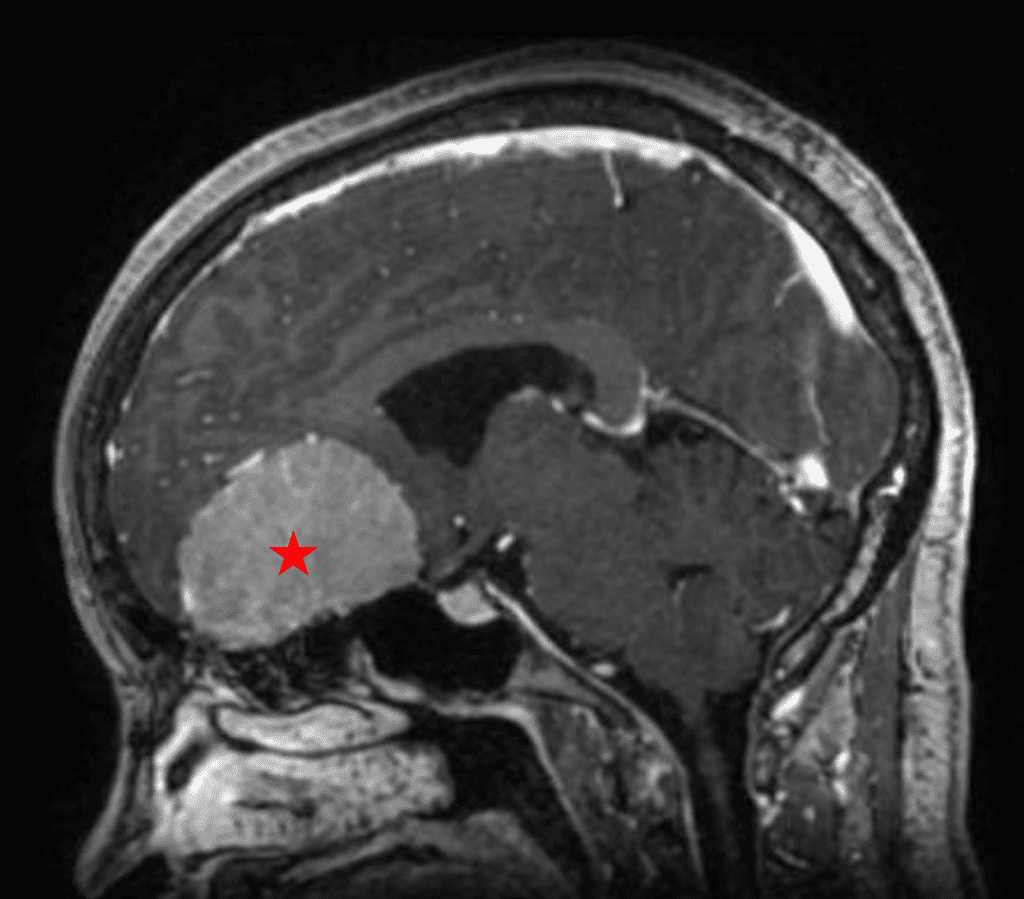

This is a 49-year-old otherwise healthy female who presented with bifrontal and retro-orbital headaches, behavioral changes, and forgetfulness. Symptoms have been progressively worsening over the past month. Her neurologic exam revealed a pronator drift, otherwise was unremarkable. MRI brain demonstrated a large extra-axial homogeneously enhancing mass of the anterior cranial fossa, resulting in significant mass effect and vasogenic edema (Figure 1a and 2a). Imaging was most consistent with a planum sphenoidale meningioma. She was referred to Dr. Xavier Gaudin for neurosurgical evaluation.

Figure 1a – Preoperative MRI demonstrating an extra-axial enhancing mass of the anterior cranial fossa.